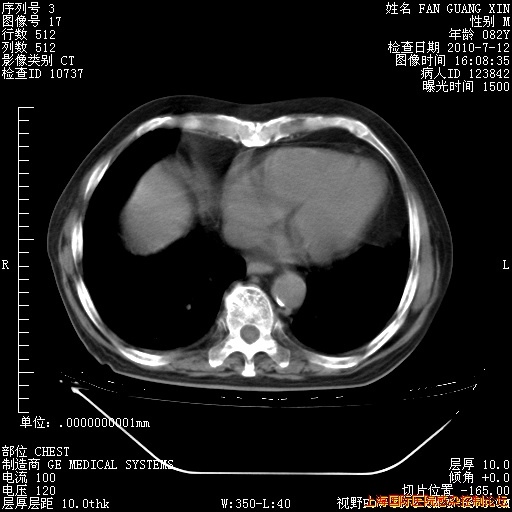

6月12日肺窗

6月12日纵膈窗